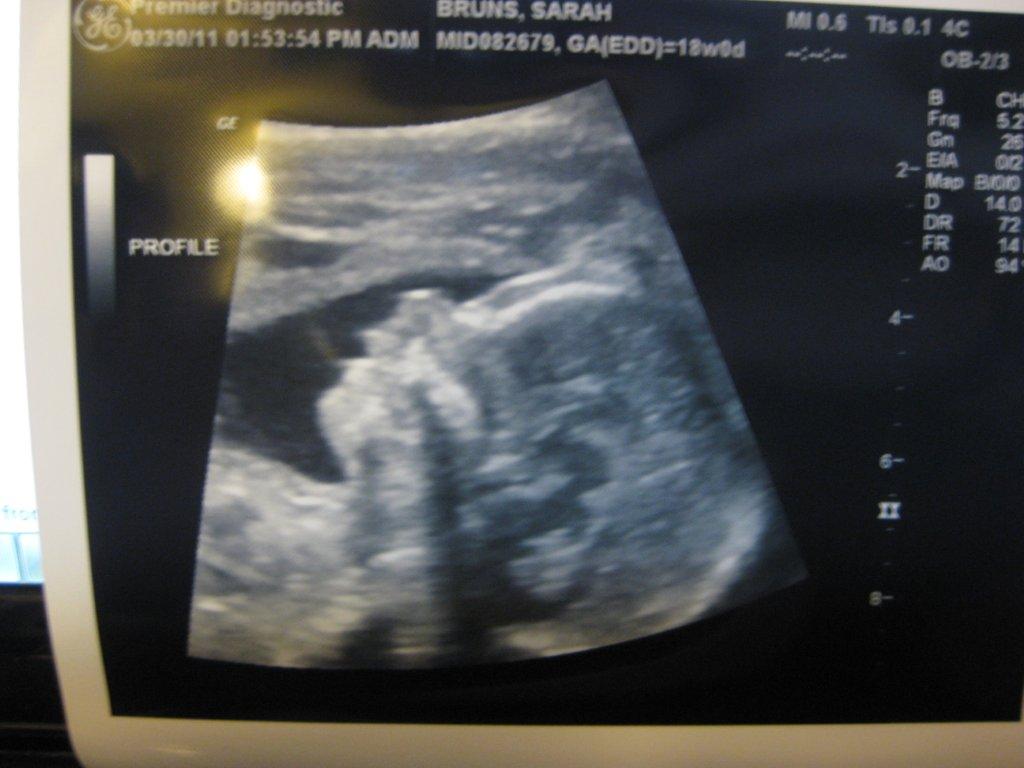

Images of When Can You See Heartbeat On Abdominal Ultrasound

Pictures of When Can You See Heartbeat On Abdominal Ultrasound